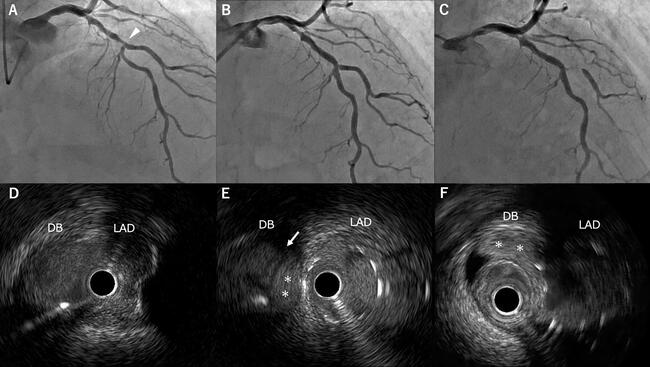

An 81-year-old man with prior myocardial infarction underwent follow-up coronary angiography, which showed severe mid-left anterior descending artery (LAD) stenosis with the first diagonal branch arising from the lesion (Figure A). Percutaneous coronary intervention was performed with diagonal branch protection. After predilatation and drug-eluting stent implantation, angiography showed Thrombolysis in Myocardial Infarction (TIMI)-3 flow (Figure B), but intravascular ultrasound (IVUS) revealed an intimal flap and small hematoma at the diagonal branch ostium (Figure E, Video 1). Shortly after transfer to recovery, the patient developed chest pain with ST-segment elevation. Emergent angiography demonstrated sub-occlusion of the diagonal branch (Figure C), and IVUS confirmed a large hematoma extending from the branch orifice (Figure F, Video 2). A drug-eluting stent was successfully deployed in the diagonal branch, restoring TIMI-3 flow.

Although side-branch occlusion after main-vessel stenting is uncommon, it can lead to serious complications such as myocardial infarction or arrhythmia. This case illustrates that IVUS can identify intimal dissection or hematoma—lesions that may not be apparent angiographically—and thereby predict imminent branch occlusion. When IVUS reveals side-branch injury, adjunctive strategies such as bail-out stenting or cutting-balloon fenestration should be considered.